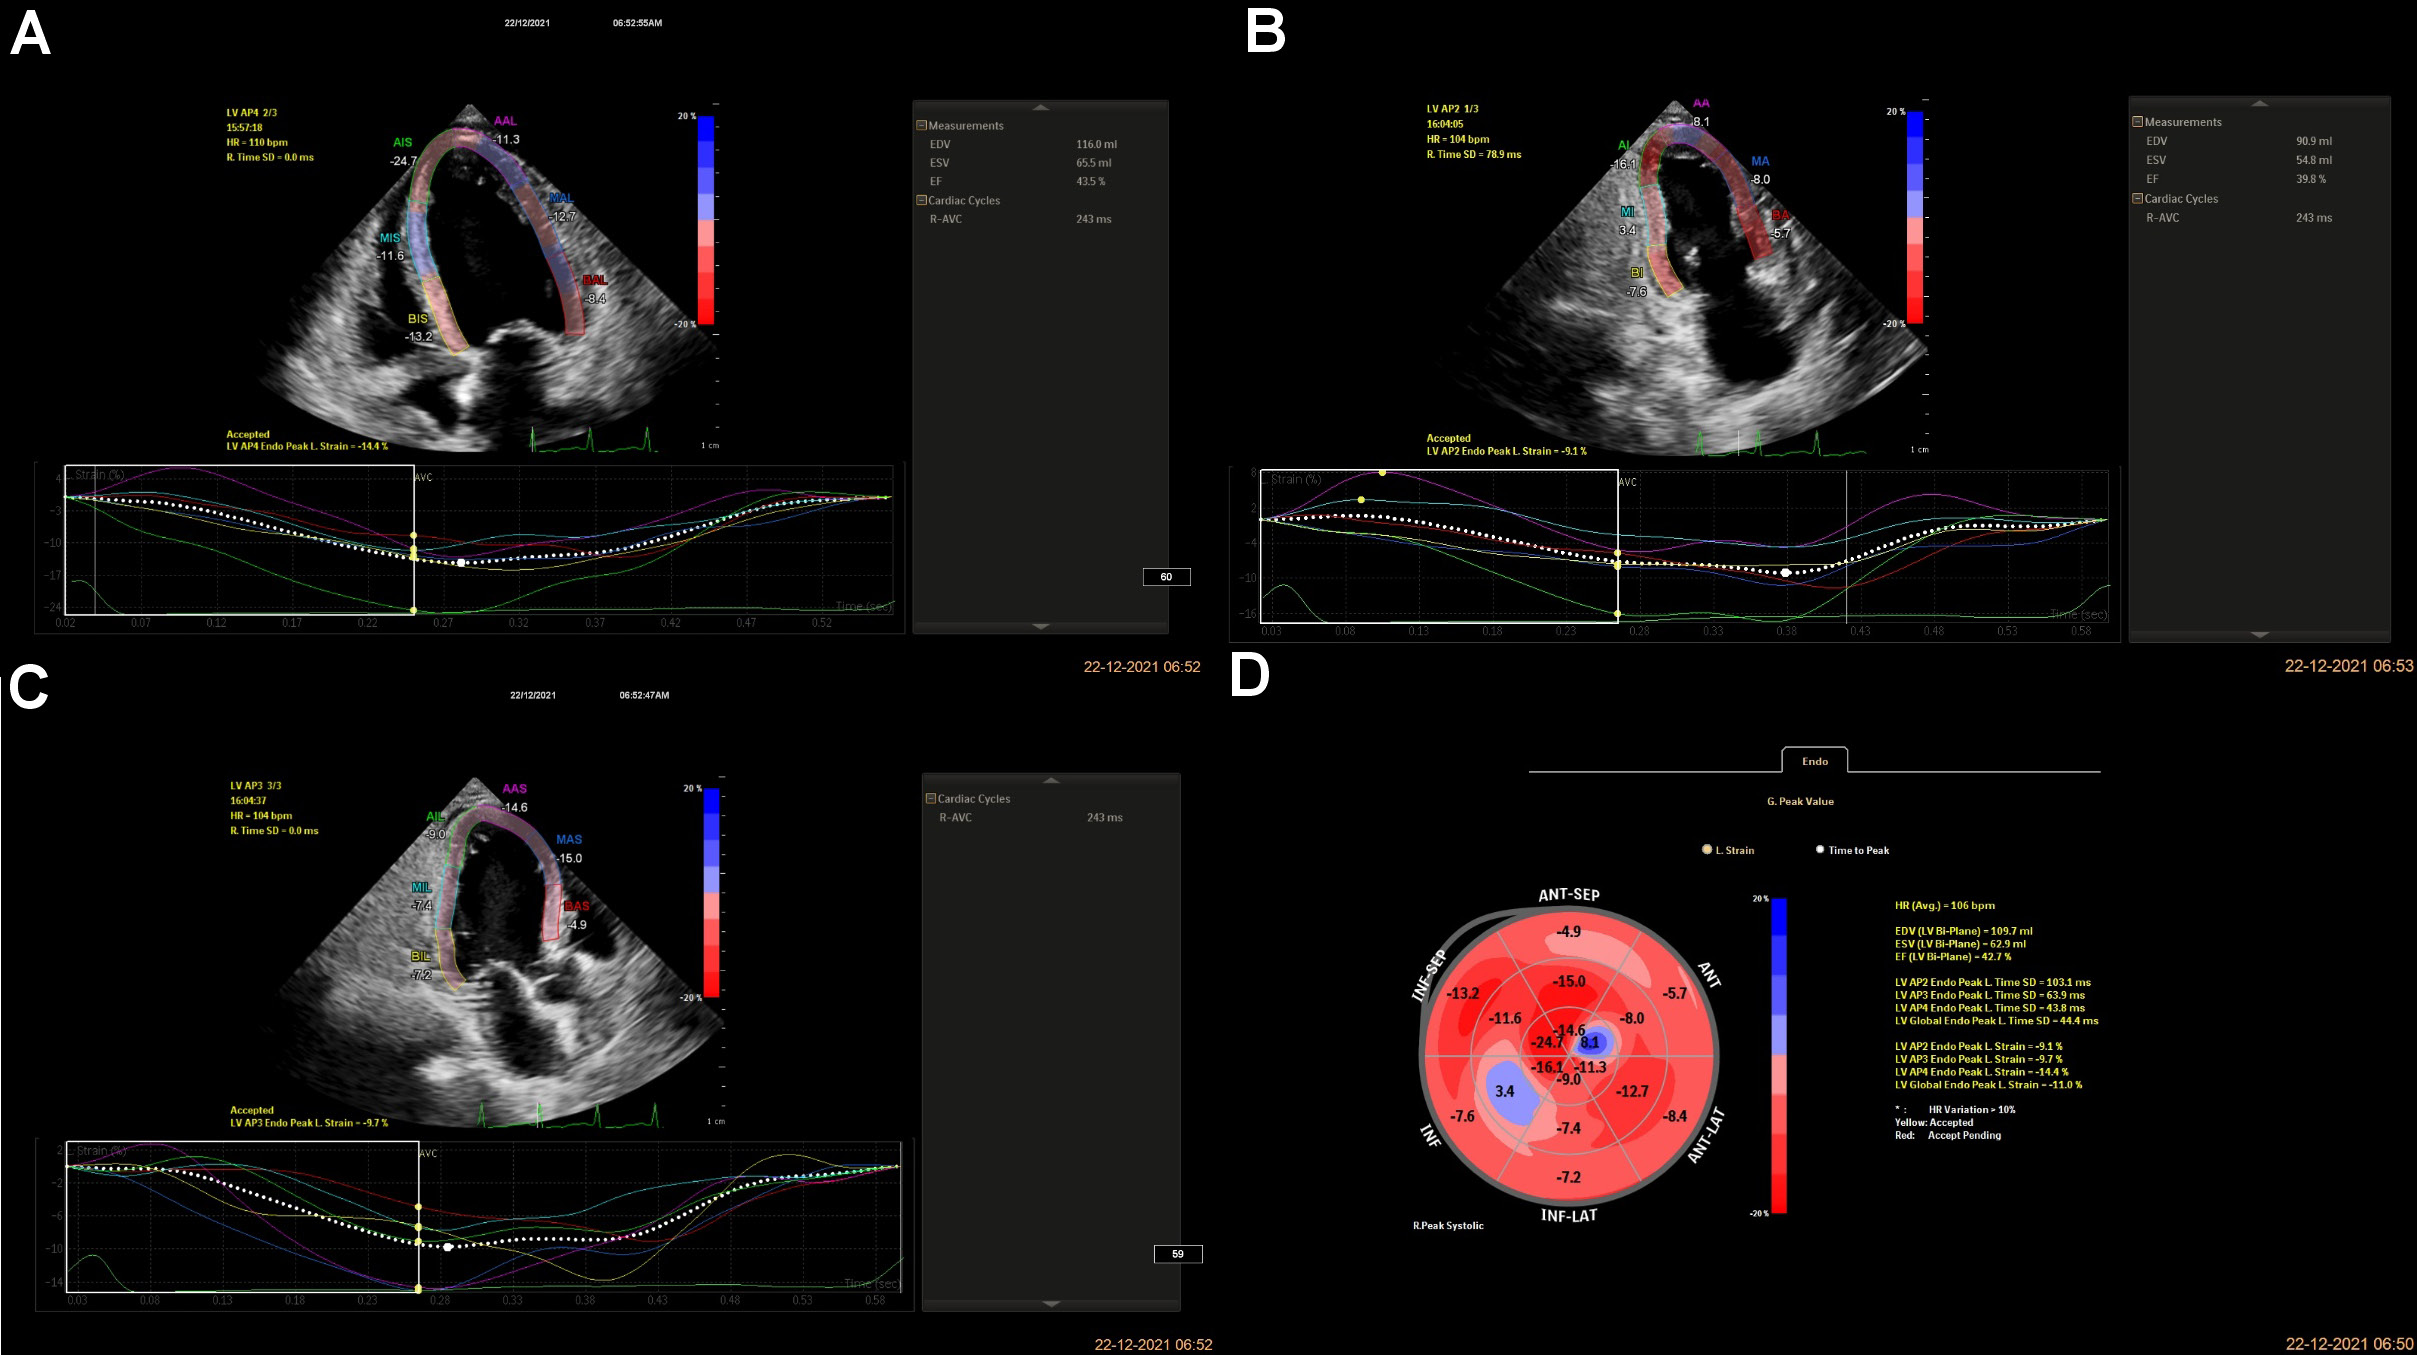

The patients were allowed to relax for 30 min before starting the procedure. A Doppler echocardiogram (EPIQ 7C 2.0.2.; Philips Healthcare, Andover, USA) with a transducer probe (X5-1 3D probe; frequency: 93 Hz) was used to evaluate the myocardial strain. The transducer probe was placed by a blinded examiner on the chest or abdomen of the subject to get various views of the heart using ultrasound. The GLS imaging is made in standard apical two-, three- and four-chamber views. The images were displayed on a monitor for real-time viewing and recorded by marking 3 specific points (the apex, the base and the septum, i.e., LVAP4, LVAP2 and LVAP3) manually within the myocardium. LVAP4, LVAP2, and LVAP3 represent LV apical four-chamber, two-chamber, and three-chamber views, respectively, and tracking these Doppler points enables the measurement of the strain rate by the machine (Figure 2). LVAP4 represents the longitudinal strain in a four-chamber view, LVAP2 represents the longitudinal strain in a two-chamber view and LVAP3 represents the longitudinal strain in a three-chamber view. The GLS is calculated as the average from all segments to measure the global LVF. The GLS rate was derived using the following formula (Equation 2) and expressed as percentage16:

Multiple linear regression modeling suggested that LVAP4 was a statistically significant predictor of GLS in group A, and LVAP3, LVAP4 and EF were statistically significant predictors of GLS in group B (Table 2andTable 3). In both groups, age showed a significant positive correlation with GLS, whereas PISA had no association with GLS (p > 0.05) (Table 4 and Table 5). The correlations are presented in Figure 3 and Figure 4. The regression model resulted in 88% (R = 0.88) of change in GLS for group B (Table 2).